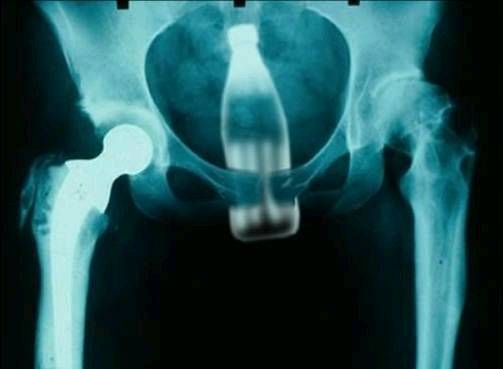

The Funny Images Thread

(thought a change was due. Explanation about this photo below...)

rectal FB